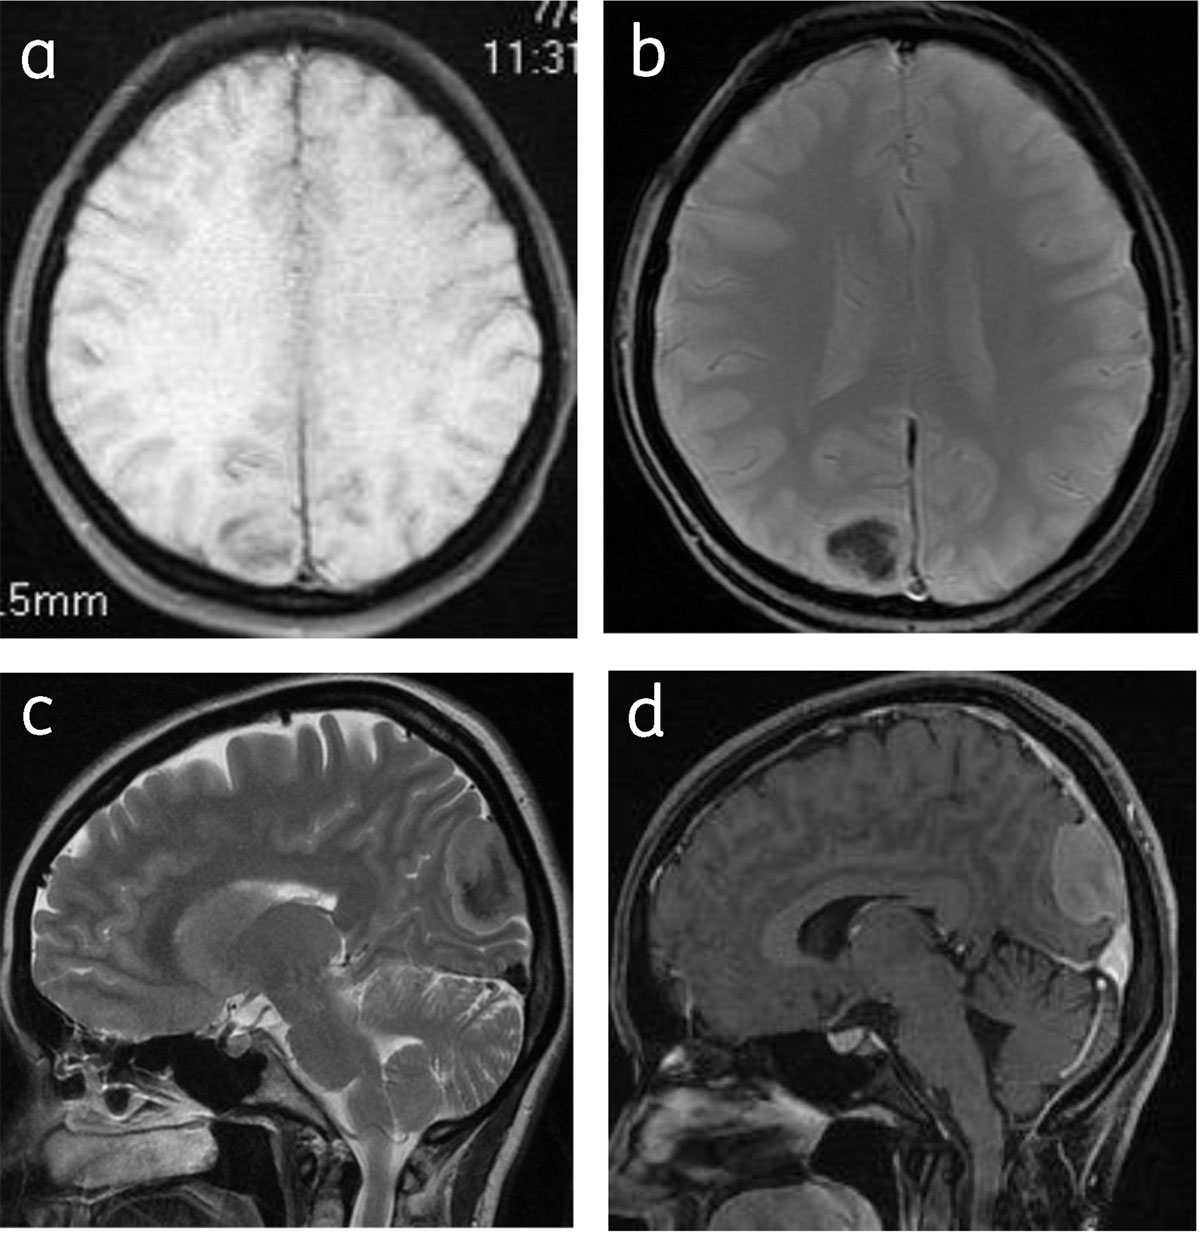

Figure 3

Calcified meningioma: Axial T1WI (a), T2* gradient (b), sagittal T2W (c) and sagittal post contrast (d) images shows right parafalcine calcified meningioma with hypointense central signal.